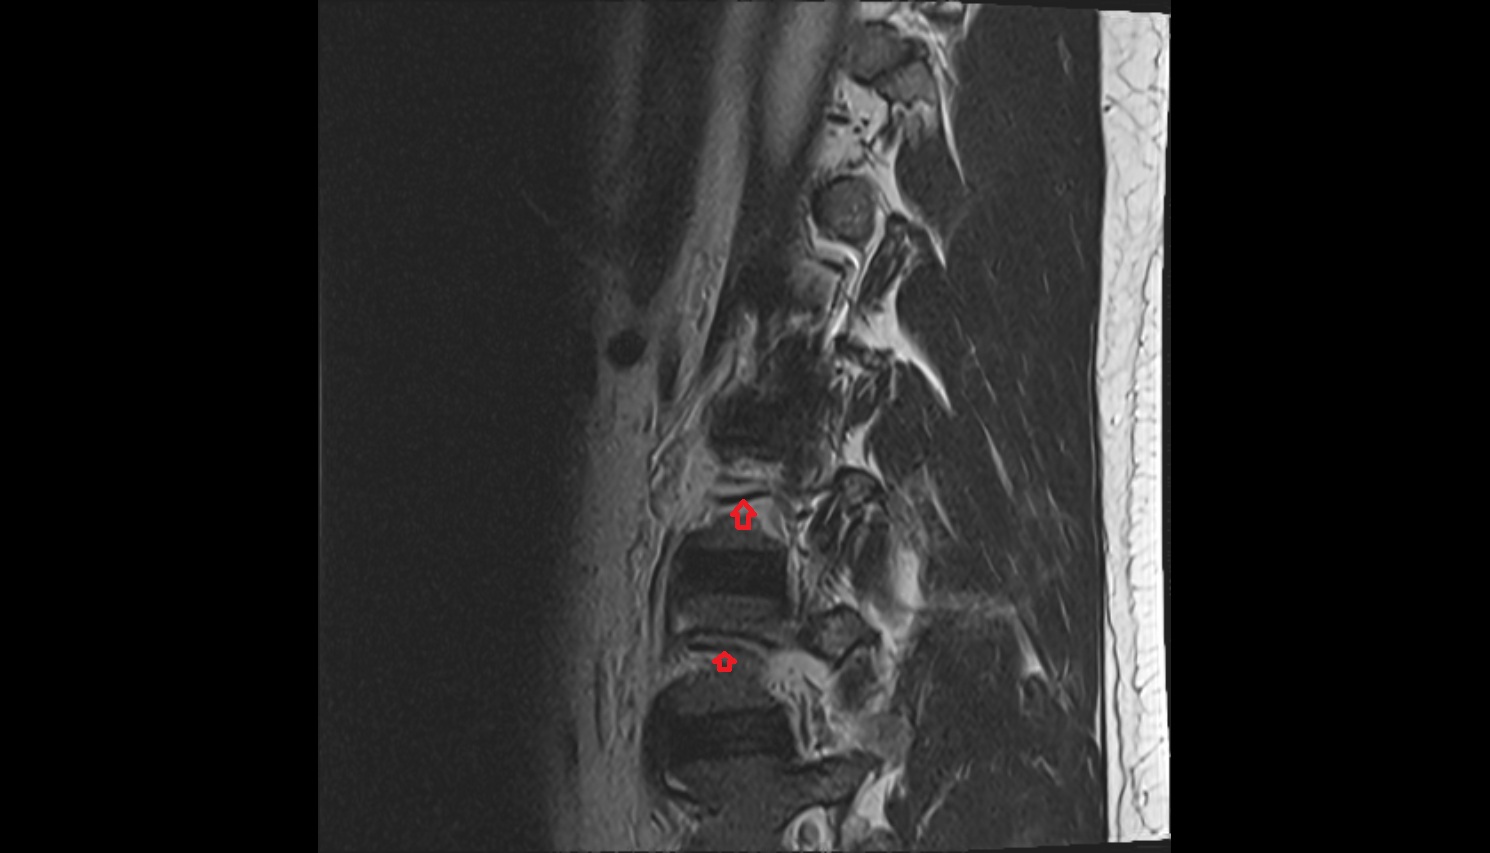

- Cauda equina

- Conus medullaris

- Traversing nerve root of spinal nerve

- Exiting nerve root of spinal nerve